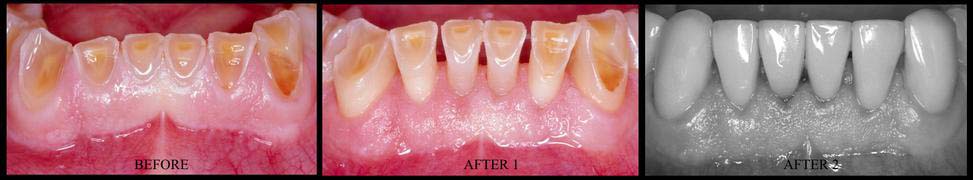

- GUM REGENERATION/GRAFTING FOR RECEDING TISSUES --> GINGIVAL RECESSION THERAPY